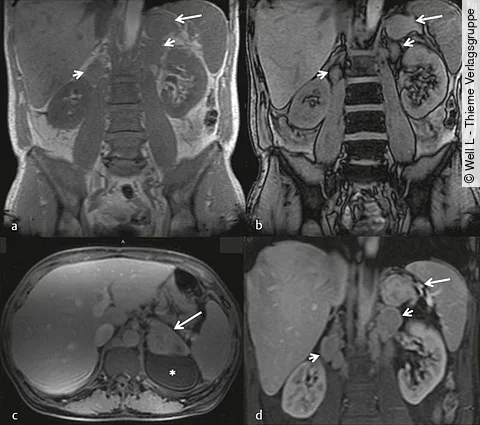

Ein 57-jähriger Mann stellt sich mit Müdigkeit, Gewichtsverlust und  Nachtschweiß vor. In der Laboruntersuchung wurden eine normozytäre Anämie, Hypoalbuminämie, erhöhtes CRP und eine Leukozytose festgestellt.